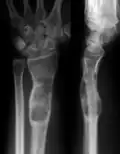

| X-ray image showing enchondromas localized in the lower part of the radius of a 7-year-old girl with Ollier disease. | |

-

X-ray showing enchondromas localized in the lower part of the radius of a 37-year-old patient affected with Ollier disease -